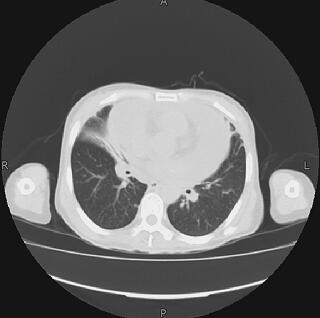

患者于4月12日转入病房治疗。当天实验室检查:血常规:WBC 10.09×109/L,N 80.4%,RBC 4.06×1012/L,ALB 94g/L;生化ALB 33.6g/L,γ-GT 69IU/L,其余异常生化指标均好转;心电图较前无明显变化;胸片较前无明显变化(图1);胸部CT:大量心包积液,左肺中叶密度增高影(图2)。

图2 胸部CT:大量心包积液,左肺中叶密度增高影

2.胸部CT:大量心包积液,左肺中叶密度增高影。